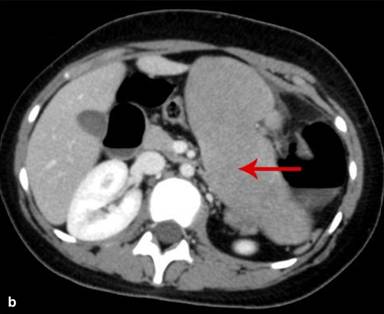

Figure 4. Axial CT scan abdomen shows an enlarged wandering spleen (red arrow), extending from the undersurface of the left lobe of the liver (a.) extending medially to the distended stomach up to the lower pole of the left kidney (b.). |

|